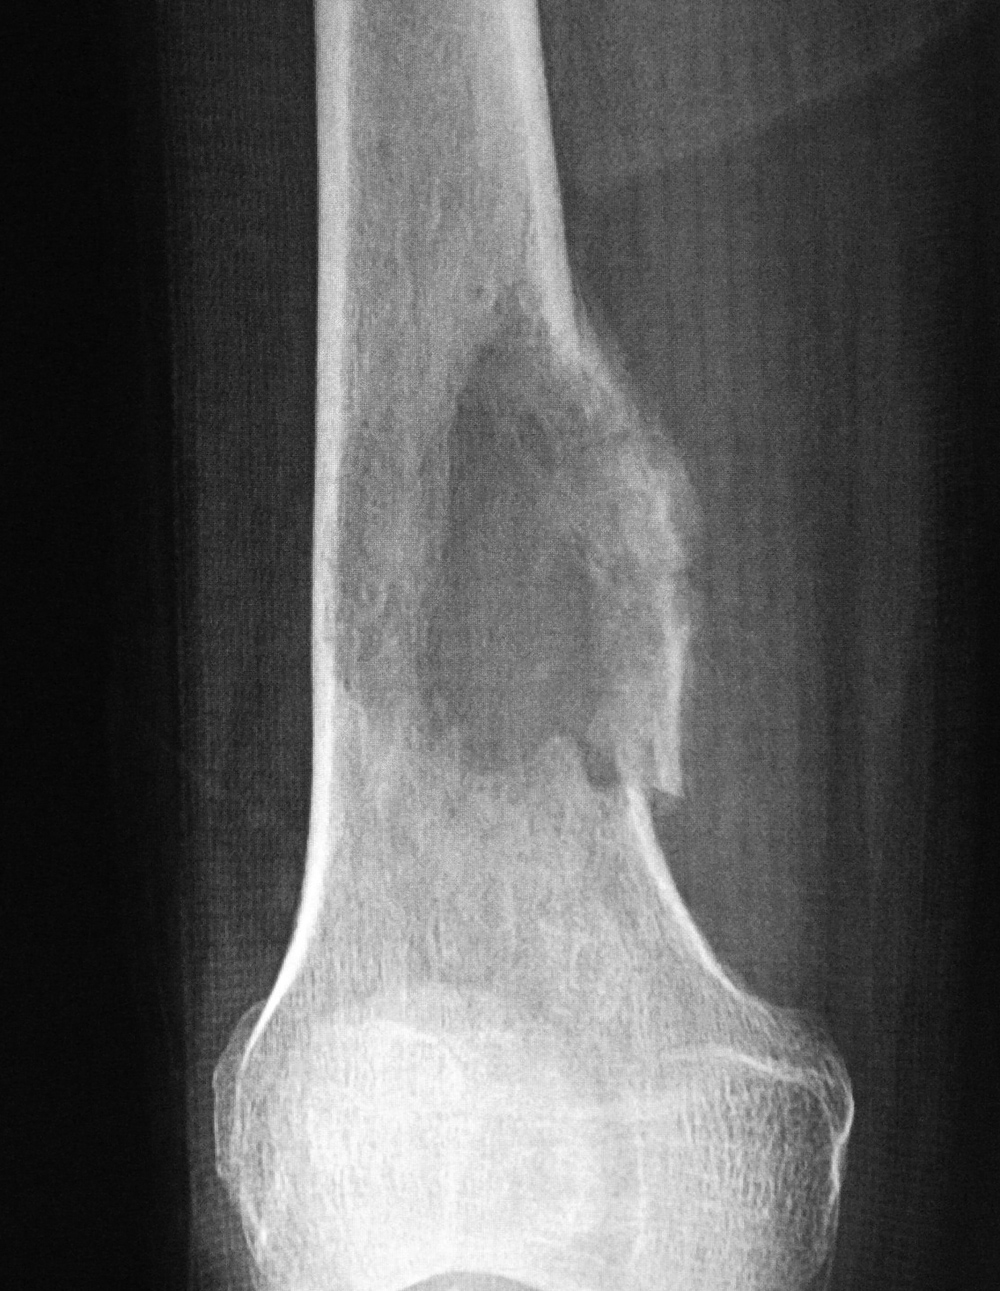

43 year-old man with comminuted right tibia and fibula fractures as well as extensive bone loss and soft tissue injury. A tibial intramedullary nail with proximal and distal locking screws is present as well as multiple rounded bony allografts. There are also large skin staples.